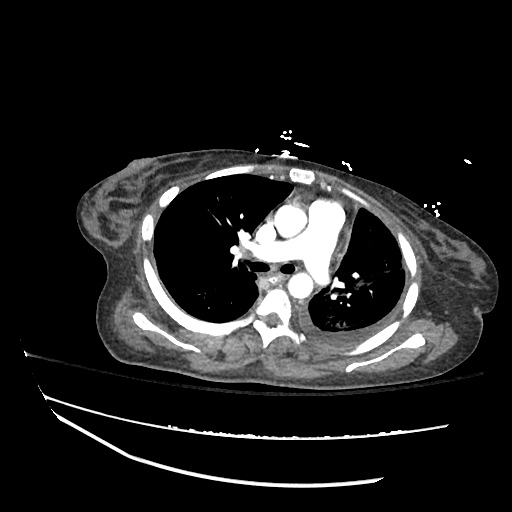

Pleural based mass Radiology Cases Radiology Pleural Tag Chest radiography and us help detect pneumothorax with various signs, and ct can also help assess the causes. Pleural tags were defined as linear strands that extended from the nodule surface to a pleural surface and were classified into three. Juxtapleural lung nodules can be defined by their location within 15 mm of a pleural surface. Radiology Pleural Tag.

Pleural based mass Radiology Cases Radiology Pleural Tag Pleural tags were defined as linear strands that extended from the nodule surface to a pleural surface and were classified into three. Juxtapleural lung nodules can be defined by their location within 15 mm of a pleural surface. Chest radiography and us help detect pneumothorax with various signs, and ct can also help assess the causes. Radiology Pleural Tag.

Pleural based mass Radiology Cases Radiology Pleural Tag Juxtapleural lung nodules can be defined by their location within 15 mm of a pleural surface. Chest radiography and us help detect pneumothorax with various signs, and ct can also help assess the causes. Pleural tags were defined as linear strands that extended from the nodule surface to a pleural surface and were classified into three. Radiology Pleural Tag.